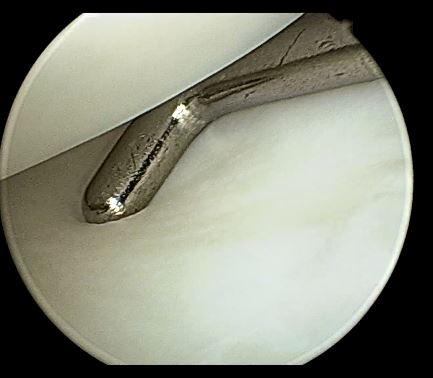

使用蓝钳等关节镜器械,修整半月板,切除中央部

盘状半月板成形后为正常的“半月”形